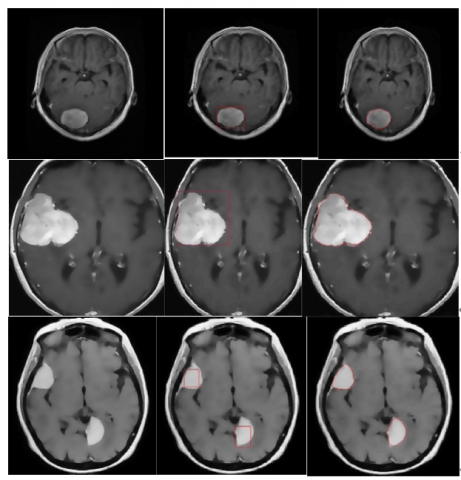

5.2 Results of the DRLSE model simulated on MATLAB for medical images

Medical images present unique challenges due to their contrast variations, noise and complex anatomical structures. We illustrate the segmentation results of these images with the DRLSE algorithm, adjusting the weighting parameters (α, λ, and μ) seen in Eq. (6), to evaluate their impact on segmentation efficiency.

5.2.1 Adjustment of Parameters α, λ, and μ

Adjustment of Parameter α Figure 6 shows the results of the DRLSE algorithm on the image from the "Brain Tumor Data" database with different values of α, with 100 iterations.

For low values of α such as α=0.5, the contour evolves slowly, creating a conservative segmentation that closely follows the initial contours, ideal for capturing fine details. For medium values of α, such as α=1.5, these values accelerate contour evolution, allowing for fast segmentation suitable for medium-sized objects. A high value for α (α=2.5) intensifies contour evolution, allowing expansive or contractive segmentation suitable for very large objects.

The α parameter should be positive for outer contours and negative for inner contours to ensure accurate segmentation.

Figure 6. Results of the DRLSE algorithm on a medical image

Adjustment of λ Parameter Figure 7 shows the results of the DRLSE algorithm on a medical image with various values of λ with 100 iterations. For low values of λ (λ=1), the contour follows the fine details and noise of the image, resulting in more irregular contours suitable for objects with complex edges. A moderate value such as λ=5 promotes smoother and more regular contours, suitable for objects with clear and well-defined edges. A high λ value (λ=8) produces very smooth and refined contours, particularly suited for segments that require maximum edge precision and significant noise reduction.

Figure 7. Segmentation results on a medical image

μ Parameter Adjustment Figure 8 shows the results of segmentation on a medical image by varying the values of μ and 100 iterations.

mu = 0.02

mu = 0.04

mu = 0.5

Figure 8. Results of the DRLSE algorithm on a medical image with different values of μ

For low values of μ, e.g. μ=0.02 distance regularization is minimized, allowing abrupt variations in the level set function. This can accelerate adaptation to local variations but risks introducing instability and artifacts.

For medium values of μ (μ=0.04), we offer a balanced compromise between stability and adaptability, ensuring a smooth level set function while allowing some flexibility to follow local variations.

A high μ value (μ=0.5) implies strong distance regularization, maintaining a very regular level set function and avoiding abrupt changes. This ensures robust convergence but limits the local adaptability of the algorithm.

The specific parameters and equations influence how the level set curve evolves, optimizing segmentation for more precise and detailed results.